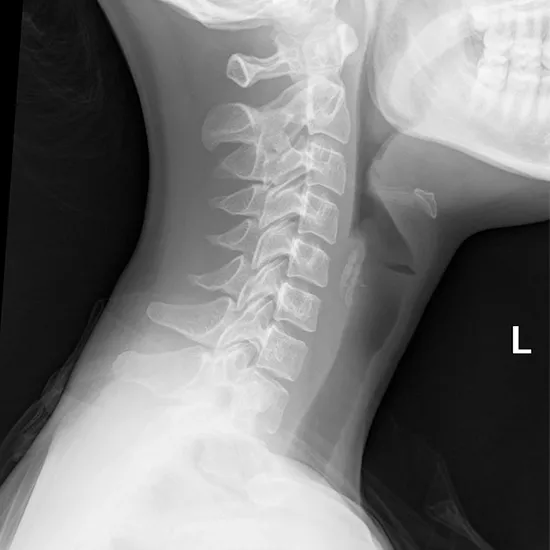

X-ray Soft Tissue Neck AP View

An X-ray technologist will photograph the patient's neck from the frontal perspective (anteroposterior or AP view).

A neck X-ray may detect soft-tissue abnormalities. Symptoms like stridor, barking cough, and hoarseness may be caused by airway enlargement. A neck X-ray may identify an enlarged epiglottis (epiglottitis). It may also help identify a throat infection.

A neck X-ray may detect enlarged tonsils and adenoids in children with sleep apnea, snoring, or sinus and ear infections.